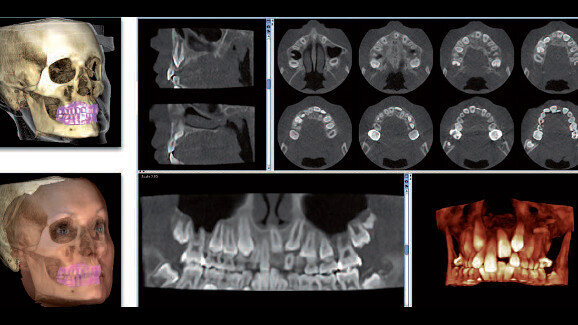

Units in the Planmeca ProMax 3D family offer the unique Planmeca Ultra Low Dose imaging protocol, which enables CBCT imaging with an even lower patient radiation dose than standard 2-D panoramic imaging. This pioneering imaging protocol is based on intelligent 3-D algorithms developed by Planmeca and yields a vast amount of detailed anatomical information at a very low patient dose.

The protocol can be used with all voxel sizes and in all imaging modes from Normal to Endodontic mode. Using the Planmeca Ultra Low Dose protocol reduces the effective patient dose by up to 75–80 per cent. Ultra low dose images are ideal for many clinical cases, such as orthodontics, post-operative and follow-up images in maxillofacialsurgery, airway studies, sinus studies and implant planning.

The latest imaging protocol with a specific associated algorithm is called the Planmeca Ultra Low Dose protocol. In medical terms, it allows radiologists to adjust imaging parameters individually according to the clinical needs of each case. The values, in particular, can be individually adjusted and reduced for each patient, as it is required according to all international scientific guidelines. Therefore, it is possible to further reduce the effective dose significantly by using the Planmeca Ultra Low Dose protocol.

Depending on the field of view, nowadays CBCT equipment with a Planmeca Ultra Low Dose algorithm has an effective dose between 4 to 22 or 10 to 36 µSv. Our patients and referring colleagues are always happy to hear that the effective dose for certain indications is now even lower than in traditional 2-D X-ray imaging. Since last year, we have been able to replace the common CBCT protocols with the Planmeca Ultra Low Dose protocol. At MESANTIS 3D Dental-Radiologicum in Germany, the Planmeca Ultra Low Dose imaging protocol is used either with a small or large field of view. Using the new protocol, a lot of patients can benefit from improved 3-D diagnostics without being exposed to a higher radiation dose.